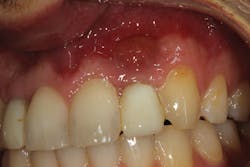

• site development to increase hard and soft tissue for pontic sites in fixed bridge prosthetics (figures 9–14);• correcting bone defects impinging upon anatomical structures after tooth extraction, such as oroantral communication (figure 18); and